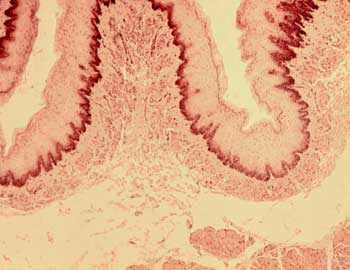

| M Esp-9 Esófago (Hematoxilina-eosina) |

Visión general: a pequeño aumento se distinguen las distintas capas del tubo esofágico. En relación con la luz observamos la mucosa, por debajo de la cual se aprecia el tejido conectivo y las glándulas de la submucosa, el armazón muscular de la pared esofágica y la fina capa adventicia periférica.

Visión específica: la mucosa aparece constituida por un epitelio pavimentoso estratificado no queratinizado que descansa sobre una membrana basal que le separa de la lámina propia conectiva rica en células linfoides. La submucosa está constituida por un conectivo laxo rico en vasos sanguíneos y glándulas tubulares mucosas. El armazón muscular presenta fibras musculares cortadas en los distintos planos alternando fibras multinucleadas estriadas y células fusiformes de núcleo central lisas. Nos encontramos pues en una sección del tercio medio del esófago. La adventicia aparece constituida por un tejido conjuntivo laxo con adipocitos y pequeños vasos sanguíneos.